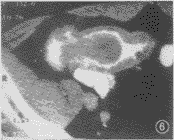

图6 嗜酸性肉芽肿继发肠套叠,于套叠头部肠腔内见椭圆形均一软组织密度肿块,边缘光滑,符合良性肿块的特征